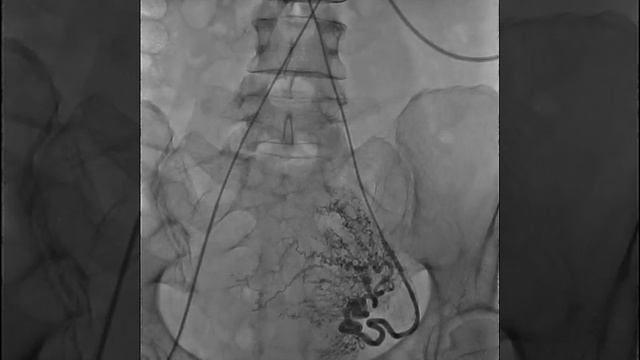

мболизация яичковой

Эмболизация яичковой 115 фото